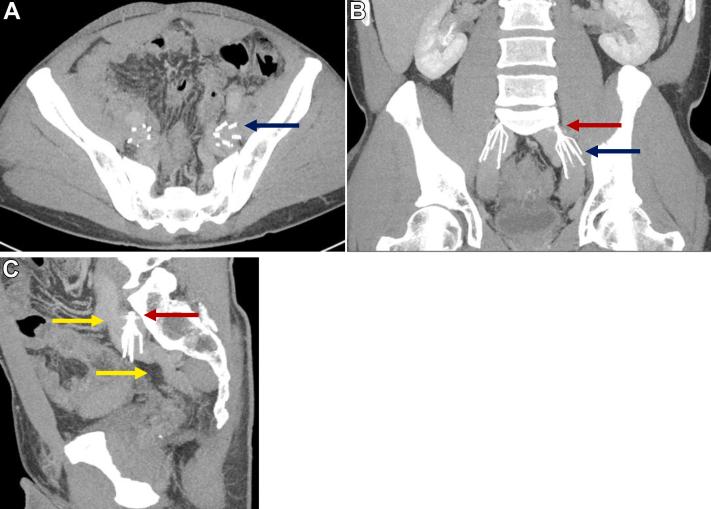

巨大腔静脉患者双侧髂静脉滤器的放置与取出

Temporary interruption of the inferior vena cava is the recommended treatment to prevent pulmonary embolism in patients with venous thromboembolism (VTE) and active contraindications for therapeutic anticoagulation. In patients with mega cava (diameter >30 mm), temporary inferior vena cava filters are contraindicated. In the present report, we have described the successful placement and retrieval of bilateral iliac vein filters in two patients with VTE, mega cava, and active contraindications for therapeutic anticoagulation. At the last follow-up, both patients had recovered without recurrent VTE and had had all filters successfully retrieved without complications.

对于静脉血栓栓塞症(VTE)且存在治疗性抗凝绝对禁忌证的患者,推荐采用下腔静脉临时阻断术预防肺栓塞。对于下腔静脉直径大于30mm的巨腔患者,禁忌使用临时下腔静脉滤器。在本报告中,我们描述了两例VTE、巨腔且存在治疗性抗凝绝对禁忌证的患者成功置入并取出双侧髂静脉滤器的情况。在最后一次随访时,两名患者均康复,无VTE复发,所有滤器均成功取出,无并发症发生。